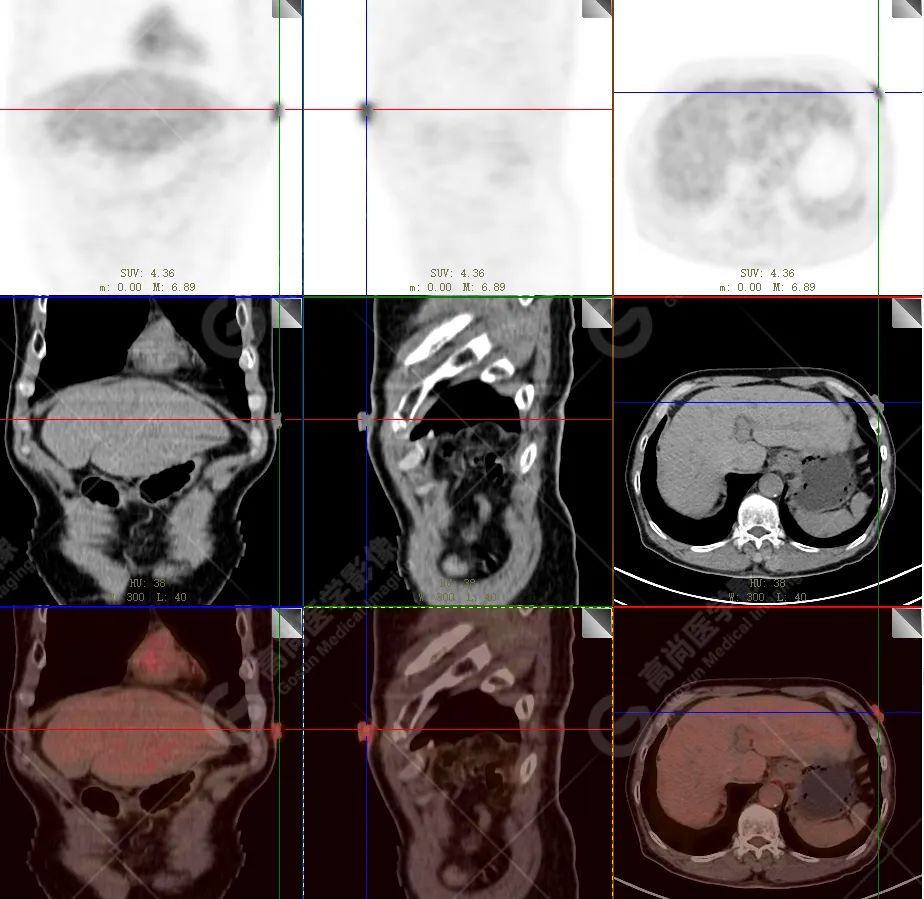

PET/CT 示:

上腭前部见一结节状放射性摄取增高影,大小约 1.6 cm×1.4 cm×1.0 cm,SUV 最大值为 10.5,CT 于上述部位见软组织密度影,边界不清,CT 值约 73 Hu(假牙金属伪影较多致 CT 值偏高)。右侧颈部(Ⅱ、Ⅲ区)及左侧颈部(Ⅰb、Ⅱ、Ⅲ区)见多发结节状及块状放射性摄取增高影,最大约 2.7 cm×2.6 cm×3.1 cm,部分放射性摄取增高,SUV 最大值为 17.7,部分病变内见放射性减低区,CT 于上述部位见增大淋巴结影。

PET/CT 结论:

1. 上腭前部结节状高代谢病灶,多考虑为恶性肿瘤(结合病史,较倾向于黑色素瘤),请结合病理学检查。

2. 右侧颈部(Ⅱ、Ⅲ区)及左侧颈部(Ⅰb、Ⅱ、Ⅲ区)多发淋巴结转移。

病理结果:

恶性黑色素瘤。